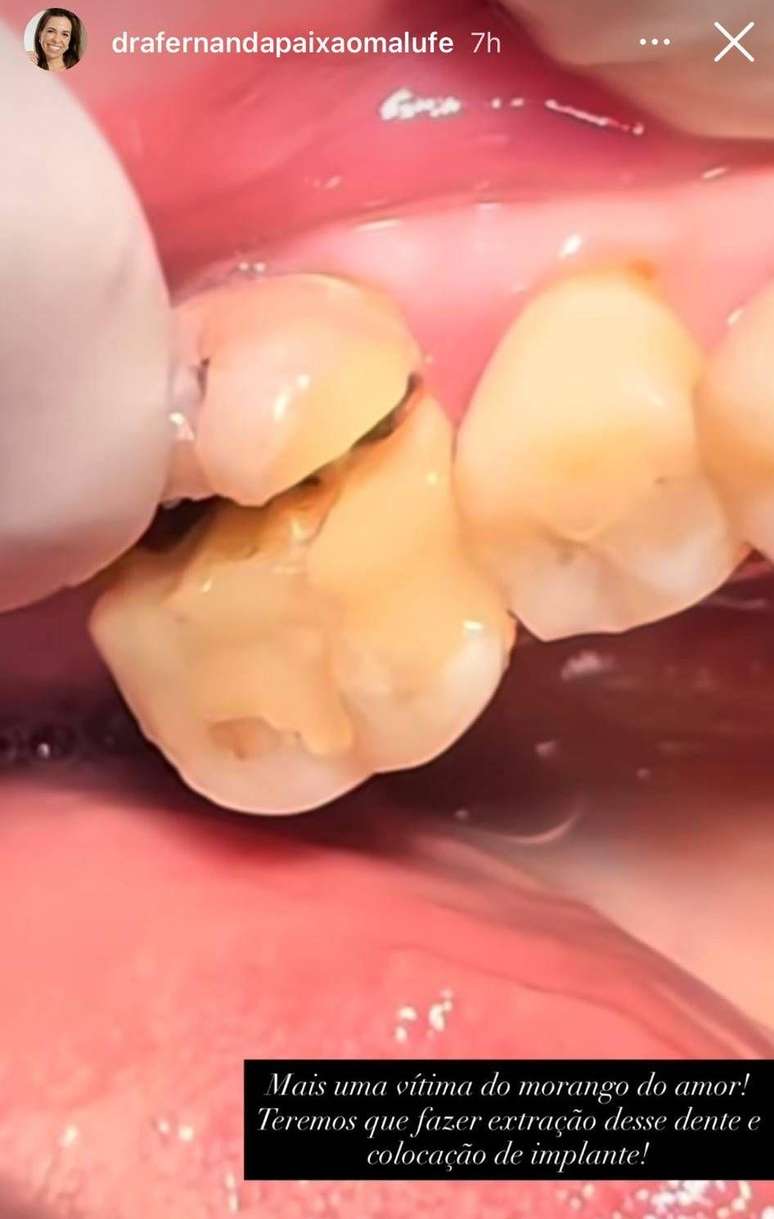

Segundo Malufe, os casos variam em gravidade: "No consultório, já atendemos pacientes que quebraram apenas um pedaço do dente, que foi possível reconstruir. Mas também tivemos casos em que a fratura atingiu a raiz — e aí não tem o que fazer: é preciso extrair o dente e colocar um implante."

Dentista mostra caso de perda dentária causada pelo consumo do 'morango do amor'

Foto: Reprodução Instagram / BBC News Brasil